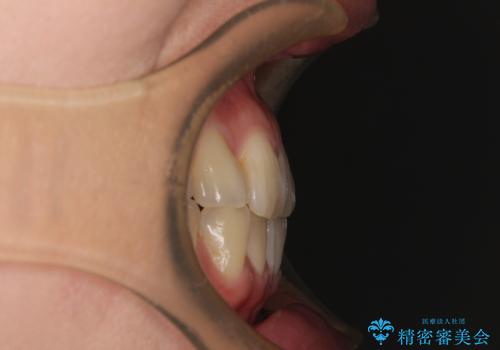

上下前歯のデコボコを気にして来院された患者様です。

ワイヤー矯正でもマウスピース矯正でも可能でしたが、短期間で、自身の手を煩わせることなく治療を行いたいとのことで、ワイヤー装置にて矯正治療を行うこととしました。

舌の突出癖により、治療過程でスペースが多くできましたが、舌のトレーニングを頑張っていただき、1年強で終えることができました。